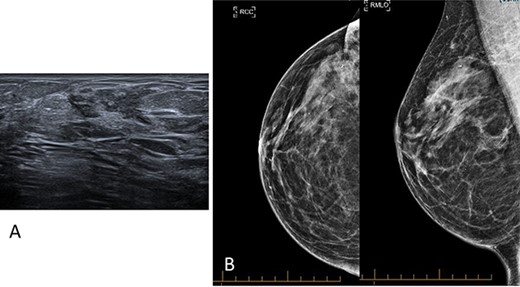

A gravida 1 para 0 (G1P0) premenopausal 31-year-old female presented with new asymmetrical firmness in the right upper outer breast. She had a history of a bilateral wise pattern breast reduction, took no regular medications and was a nonsmoker. She had a maternal family history of ovarian cancer diagnosed in fifth decade of life. Bilateral breast examination revealed no overlying skin or nipple changes, and a discrete mobile firmness in the right upper outer breast, and no palpable lymphadenopathy. The ultrasound demonstrated increased density and a glandular ridge at 9 O’clock 6 cm from the nipple of the right breast, breast imaging-reporting and data system (BI-RADS) classification score of 3 (Fig. 1A). Mammography demonstrated normal breast tissue (Fig. 1B). Core biopsy was indicative of benign breast tissue with a differential of a breast hamartoma. The patient proceeded to undergo magnetic resonance imaging for further characterization, which showed asymmetric fibrocystic change and nodular glandular tissue with enhancement across a large span (15 mm × 45 mm × 28 mm) on the right lateral breast without a focal lesion (Fig. 2). Breast malignancy could not be excluded, thus the patient proceeded to a diagnostic excisional biopsy. Histopathology revealed a 52 mm span of gynaecomastia-like change of the female breast, with a tri-layered pattern of ductal hyperplasia focally, as has previously been described in male gynaecomastia (Fig. 3) [1]. An underlying aetiology was not found on postoperative serological investigations, and the patient continued with routine breast screening as per local guidelines.

(A) Ultrasound imaging of the right breast highlighting increased density and a glandular ridge at 9 O’clock 6 cm from the nipple, BI-RADS classification score of 3. (B) Mammography imaging of the right breast demonstrating normal breast tissue.